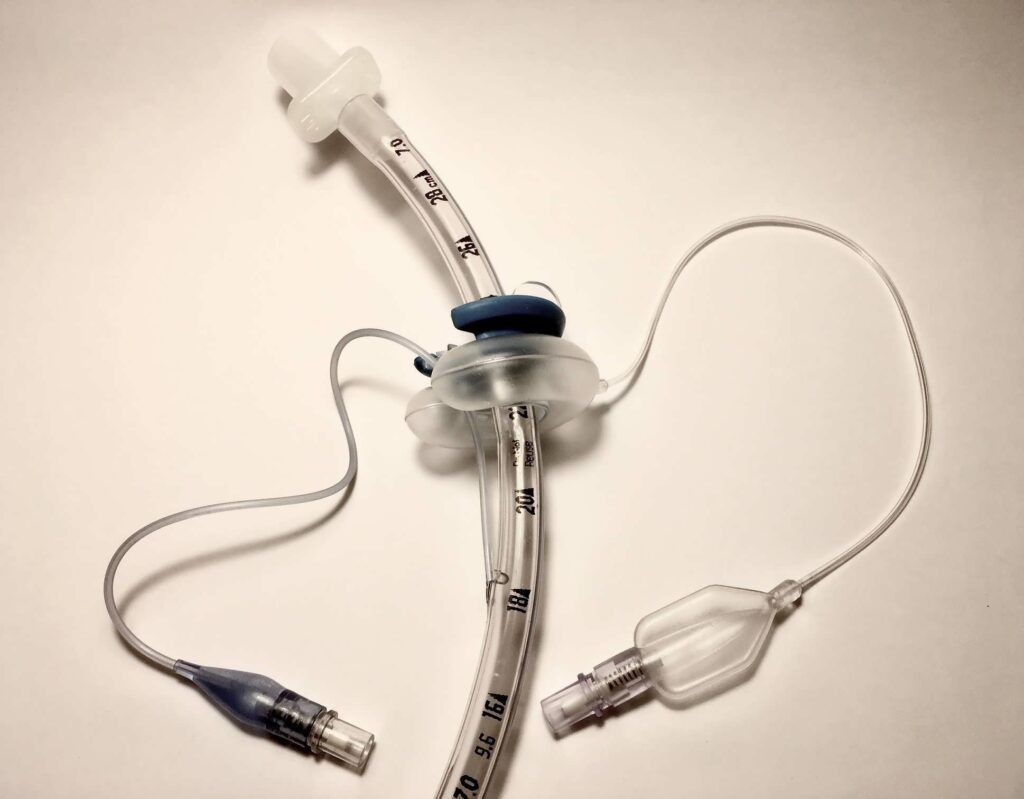

El dispositivo CLIP-FAB es un dispositivo desechable de fácil uso, que se adapta al tubo endotraqueal (ET) mediante un clip y un balón intraoral, fijándolo y evitando que se mueva o se desplace accidentalmente mientras el paciente permanezca conectado.

El dispositivo CLIP-FAB es un dispositivo desechable de fácil uso, que se adapta al tubo endotraqueal (ET) mediante un clip y un balón intraoral, fijándolo y evitando que se mueva o se desplace accidentalmente mientras el paciente permanezca conectado.

El dispositivo CLIP-FAB está compuesto por 4 piezas.

GLOBO para colocar detrás de los dientes

SOPORTE para colocar entre dientes y labios.

PINZA de fijación del TE.

Sistema de hinchado.

El dispositivo CLIP-FAB se coloca fácilmente después de la introducción del tubo endotraqueal. Una vez que el tubo endotraqueal se ha colocado en su posición definitiva, se fija lateralmente al dispositivo mediante el clip interior.

Con el inflado del globo interno, el dispositivo CLIP-FAB garantiza la fijación total de todo el sistema

(TE + CLIP-FAB) sin la necesidad de ningún otro material externo y evitando los desplazamientos.